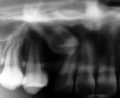

埋伏歯は、歯の萌出する隙間の不足、萌出方向の不良、萌出力不足、腫瘍または囊胞などの障害物により萌出路が塞がれている場合などに生じる病気である。いったん萌出が妨げられると、原因が除去されても自然萌出に至らないことが多く、そのままでは埋伏歯が使えないだけでなく、正常咬合が確立できない事態となる。

最良の解決策は、口腔外科的に開窓後、矯正歯科的に牽引し咬合に参加させることである。単に萌出させたと言うだけでなく、牽引後マルチブラケット装置を使用し、正常咬合を確立したケースの提示が求められている。